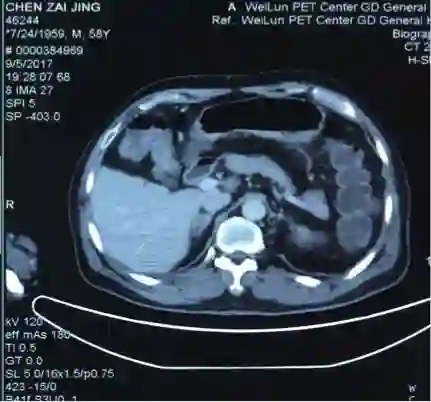

5. 2017-9-5广东省人民医院PET提示:右肺下叶肿物2.8*2.7cm,SUV 22.3,双侧颈部、双侧气管旁、隆突下、食管旁、右侧肺门淋巴结肿大,代谢升高,考虑为转移灶,右侧肾上腺转移灶,具体结果见下图:

7.目前诊断:右下肺肿瘤cT1cN3M1c IVB期(颈部淋巴结、肾上腺)

2.  根据PET/CT目前诊断为右下肺肿瘤cT1cN3M1c IVB期(颈部淋巴结、肾上腺)

谢松喜医生:很多风湿免疫性疾病淋巴结都表现为反应性增生。这个患者颈部淋巴结、纵隔淋巴结和肺门淋巴结肿大,但对于肾上腺的病灶比较难解释,肾上腺的病灶也可能是良性的腺瘤,跟前面提到的淋巴结反应性增生没关系。

吴一龙医生这个病例的PET-CT有一个特点,右肺下叶的病灶并不大,2.7*2.8cm,但是代谢非常高,高达22.3。这种小病灶高代谢的病灶,在肺癌患者中比较少见。尤其是代谢值大于20但病灶小的情况很少见。我同意谢主任刚的意见,如果该患者没有肾上腺的病灶,我认为诊断可以到此为止。我们可以看到,肺内的病灶有可能是肺内的淋巴结,我们已经对最大的淋巴结进行了活检,为良性病灶。但是,由于该患者多了肾上腺的病灶,用刚才的说法无法解释,肾上腺不属于淋巴系统。结合既往我们遇到的病例,我们现在有两个办法,我认为对于该患者,观察是一个办法,但是如果漏诊会比较麻烦,如果观察一段时间,下次过来复查提示病灶稍增大,我们如何处理?因此我认为现在我们要明确诊断,需要取病理活检,但是是取肺部病灶还是肾上腺的病灶?